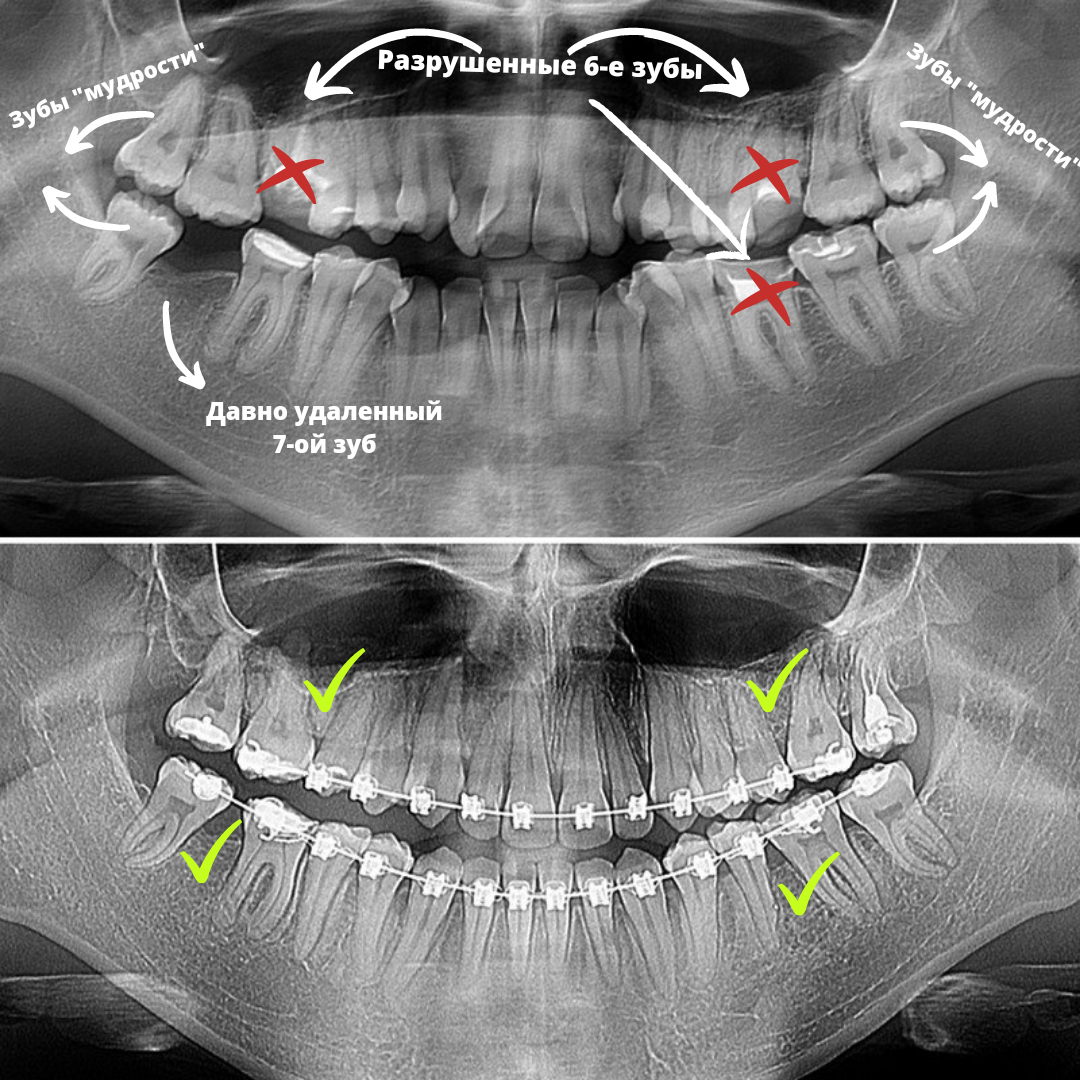

🦷 8-е зубы или зубы "мудрости" обычно прорезываются позже всех остальных зубов, где-то в 15-25 лет. Этот факт даёт им шанс дольше оставаться здоровыми.

✅ В этом клиническом примере 6-е зубы оказались разрушенными, а 7-ой и вовсе удален (на рентгеновском снимке снизу слева). А вот зубы "мудрости" оказались вполне себе хорошими! Решили замещать "мертвые" зубы "живыми", а снизу слева перемещать 8-ой на место удаленного 7-ого и таким образом избежать протезирования!